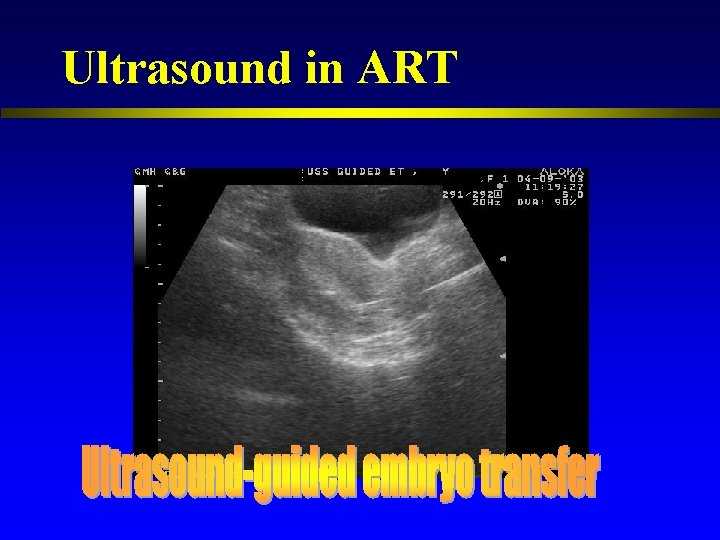

Ultrasound in ART